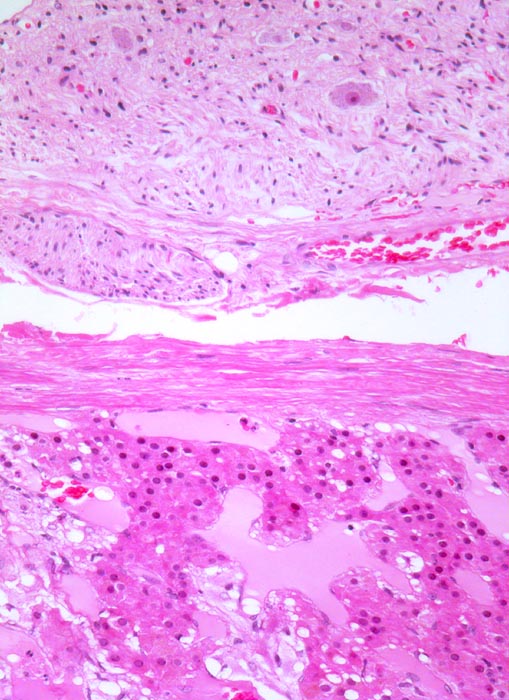

Phaeochromozytom

Nebenniere

Das Phaeochromozytom infiltriert die Nebennierenrinde. Die Nebenniere hat eine schmale bindegewebige Kapsel. Ganglion im periadrenalen Weichteilgewebe mit mehreren Ganglienzellen.

Der Patient klagt über rezidivierende Kopfschmerzen seit zirka zwei Monaten. In letzter Zeit hat er Alcacyl genommen, jedoch ohne Erfolg. Die Computertomographie des Abdomens zeigt einen 5cm grossen Tumor im Bereich der rechten Nebenniere. Die Familienanamnese für multiple endokrine Neoplasien (MEN) ist bland.